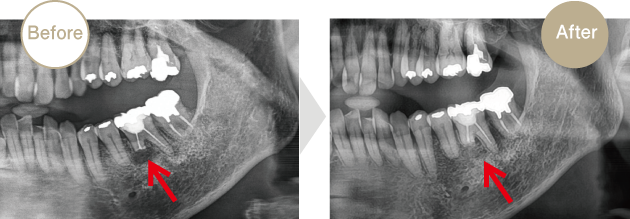

症例.02

歯根端切除術

下顎大臼歯に疼痛と腫脹を訴え来院されました。根端部に急性の炎症が認められたため消炎後、被せ物を外さずに外科処置を行い5年経過良好です。